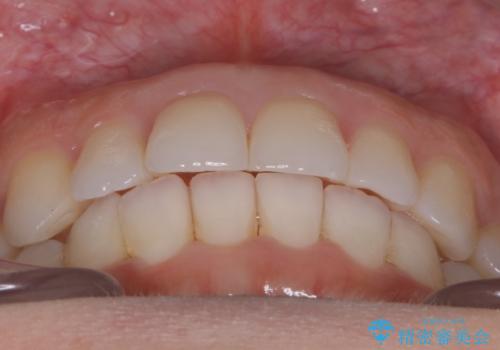

【非抜歯】前歯のガタつき マウスピースの部分矯正

- 上下の前歯の細かいガタつきの治療をご希望されて来院されました。

奥歯部分にはガタつきや噛み合わせの問題などがほとんど見られず、前歯のガタつきも軽度だったため、インビザライン ライト パッケージでの部分矯正を行うこととなりました。

今回のケースでは奥歯の噛み合わせに問題がほぼみられなかったため、前歯の位置のみに焦点を当て部分矯正を行いました。

適応されるケースが限られるものの、適応であった場合の治療期間は全体矯正と比べると格段に短くなり、費用も抑えられます。